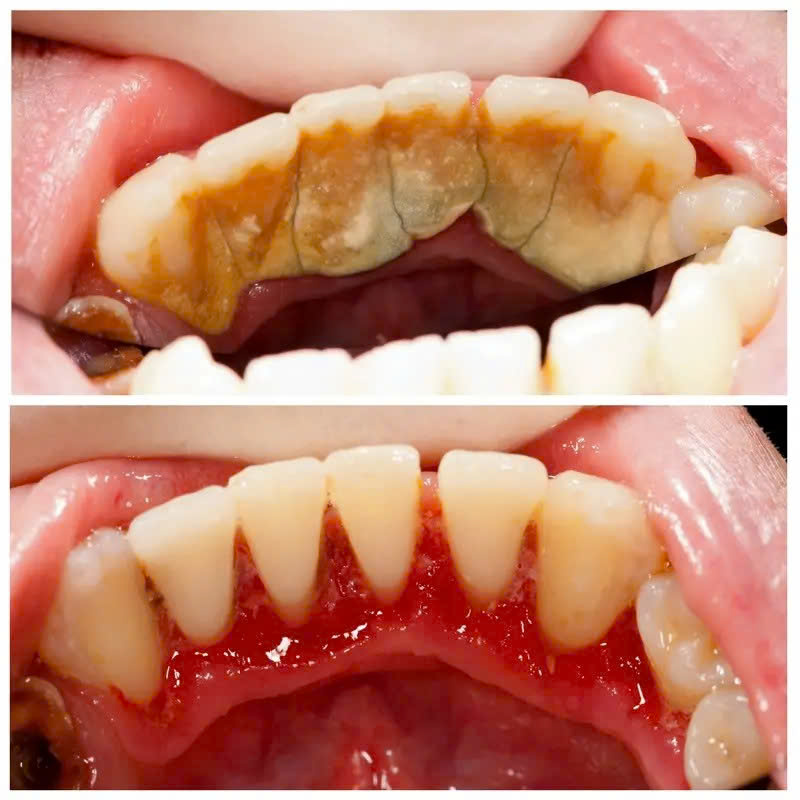

Người có mảng bám vàng nâu quanh viền nướu

Nếu bạn thấy chân răng xuất hiện lớp cứng màu vàng hoặc nâu sậm, đó không còn là mảng bám thông thường nữa – mà đã là cao răng vôi hóa. Lúc này, việc đánh răng hay súc miệng sẽ không thể loại bỏ được. Càng để lâu, vi khuẩn càng phát triển mạnh và tấn công nướu.

Người thường xuyên chảy máu chân răng khi đánh răng

Đừng vội nghĩ do bàn chải cứng hay đánh răng quá mạnh. Phần lớn nguyên nhân là do viêm nướu vì cao răng tích tụ lâu ngày. Lấy cao răng đúng cách sẽ giúp nướu khỏe hơn và giảm tình trạng chảy máu rõ rệt.

Giảm viêm nướu và chảy máu chân răng

Cao răng chính là nguyên nhân hàng đầu gây viêm nướu. Khi lớp cặn cứng được loại bỏ, môi trường vi khuẩn bị phá vỡ, nướu sẽ dần hồi phục, săn chắc và hồng hào hơn. Tình trạng chảy máu khi đánh răng cũng được cải thiện rõ rệt sau một thời gian ngắn.